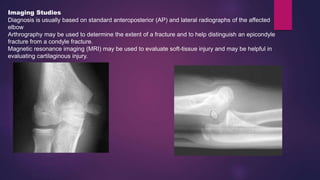

Imaging Studies

Diagnosis is usually based on standard anteroposterior (AP) and lateral radiographs of the affected

elbow

Arthrography may be used to determine the extent of a fracture and to help distinguish an epicondyle

fracture from a condyle fracture.

Magnetic resonance imaging (MRI) may be used to evaluate soft-tissue injury and may be helpful in

evaluating cartilaginous injury.